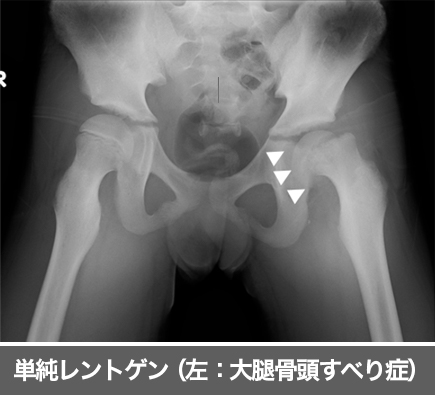

大腿骨の骨頭の先端が成長軟骨部でずれてしまう病気です。肥満やホルモン変化、X脚など様々な原因が考えられています。特に男児に多く、9歳から15歳頃の股関節の成長軟骨線が力学的に弱い時期に発症します。

骨頭すべり症に対する治療方法は原則として手術治療が選択されます。不安定な骨端線部を金属で固定する方法や骨切り術が必要な場合があります。